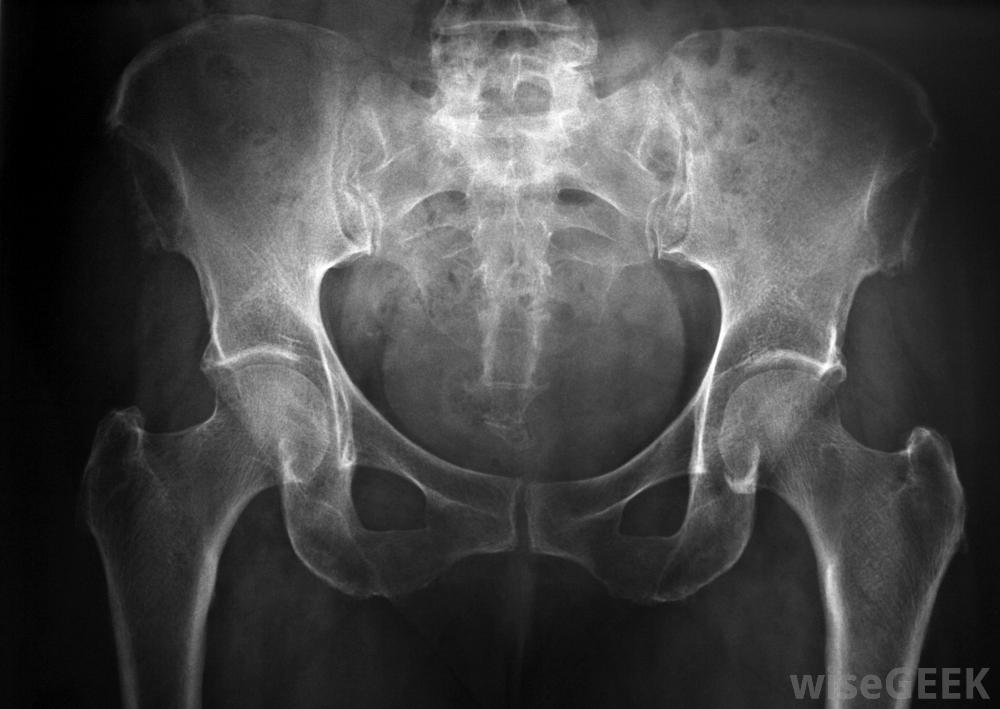

如果医生怀疑阴部神经病变,x光可以用来寻找受损的组织和神经。许多阴部神经病变的病例都是由外伤引起的,在这种情况下,腹股沟和肛门受到了很大的压力。自行车撞车,摔倒在栅栏上,或分娩特别困难都是可能的原因。在某些情况下,由于过度劳累,神经压迫会随着时间的推移逐渐发生。热衷骑自行车的人患慢性阴部神经病变的风险特别高。如果骨盆手术引起广泛肿胀或阴部神经意外受损,骨盆手术也可能导致神经病变

许多阴部神经病变的病例都是由腹股沟区紧张引起的医生在检查病人的症状和进行快速体检后可能会怀疑阴部神经病变。通常会进行X光和计算机断层扫描,以寻找骨盆中受损的组织和神经,如果不清楚的话问题在于,可能会沿着神经中的可疑部位注射局部麻醉剂,看看疼痛是否减轻。医生根据位置、性质和,阴部神经病变的严重程度。

通过医学影像扫描仔细检查骨盆,以确定疼痛原因